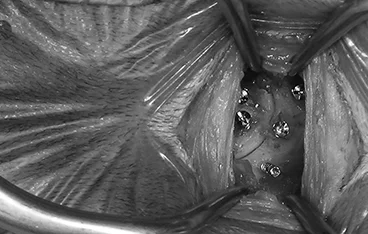

양방향 척추 내시경 BESS, Biportal Endoscopic Spine Surgery

기존의 단일 포털 내시경(uniportal endoscopy)의 한계를 극복한

정밀한 양손 작업이 가능한 최소침습 기술입니다.

리본동물의료센터 2025년 1월부터 부울경 최초로 양방향 척추 내시경을 도입해왔으며, 영남권 최다 임상 case를 축적하고 있습니다.

• 정밀한 수술 조작

• 근육 인대 손상 최소화

• 절개 최소화

• 빠른 회복과 낮은 통증

• 고배율 직시 시야 확보